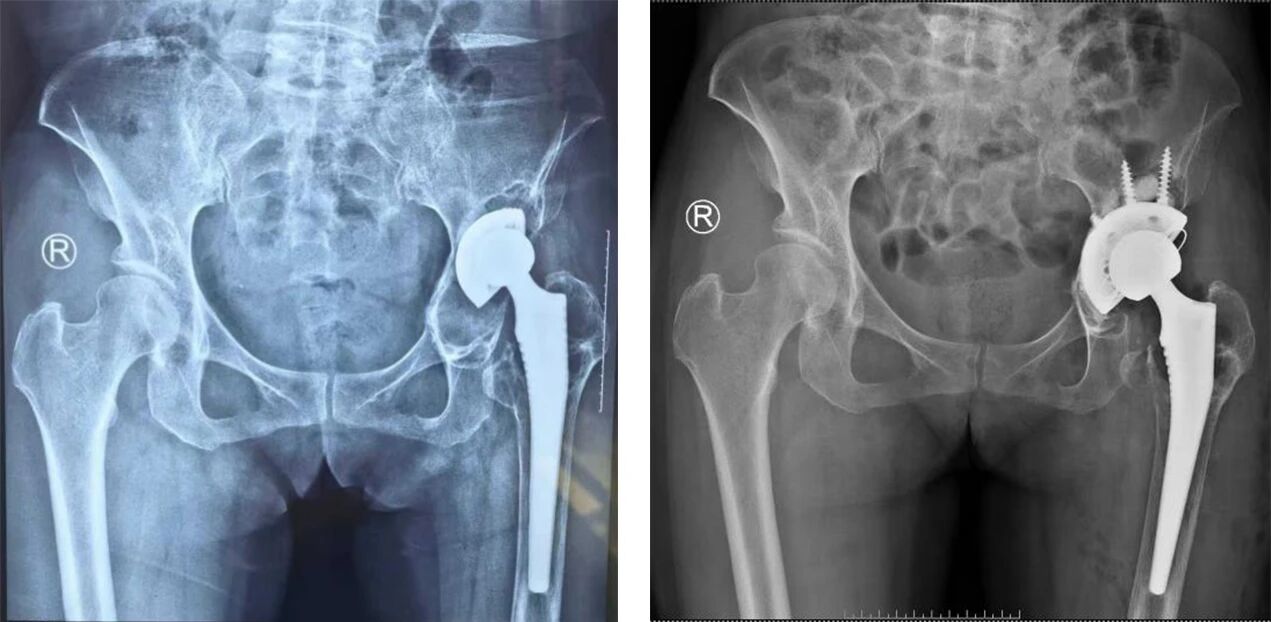

近日,驻马店市第一人民医院急诊外科成功为一名左侧人工髋关节假体松动患者实施全髋关节翻修术。57岁的关女士在11年前因左侧股骨头坏死接受人工全髋关节置换,术后恢复良好。1年前,她无明显诱因出现左髋部疼痛,并逐渐出现下肢不等长、行走跛行,经检查确诊为假体松动。

入院后,急诊外科孙海涛医生为患者进行详细查体,结合影像学检查明确诊断为髋臼侧假体松动。科室经讨论制定个性化手术方案,在麻醉科、心内科等多学科协作下,顺利完成左侧人工全髋关节翻修术。